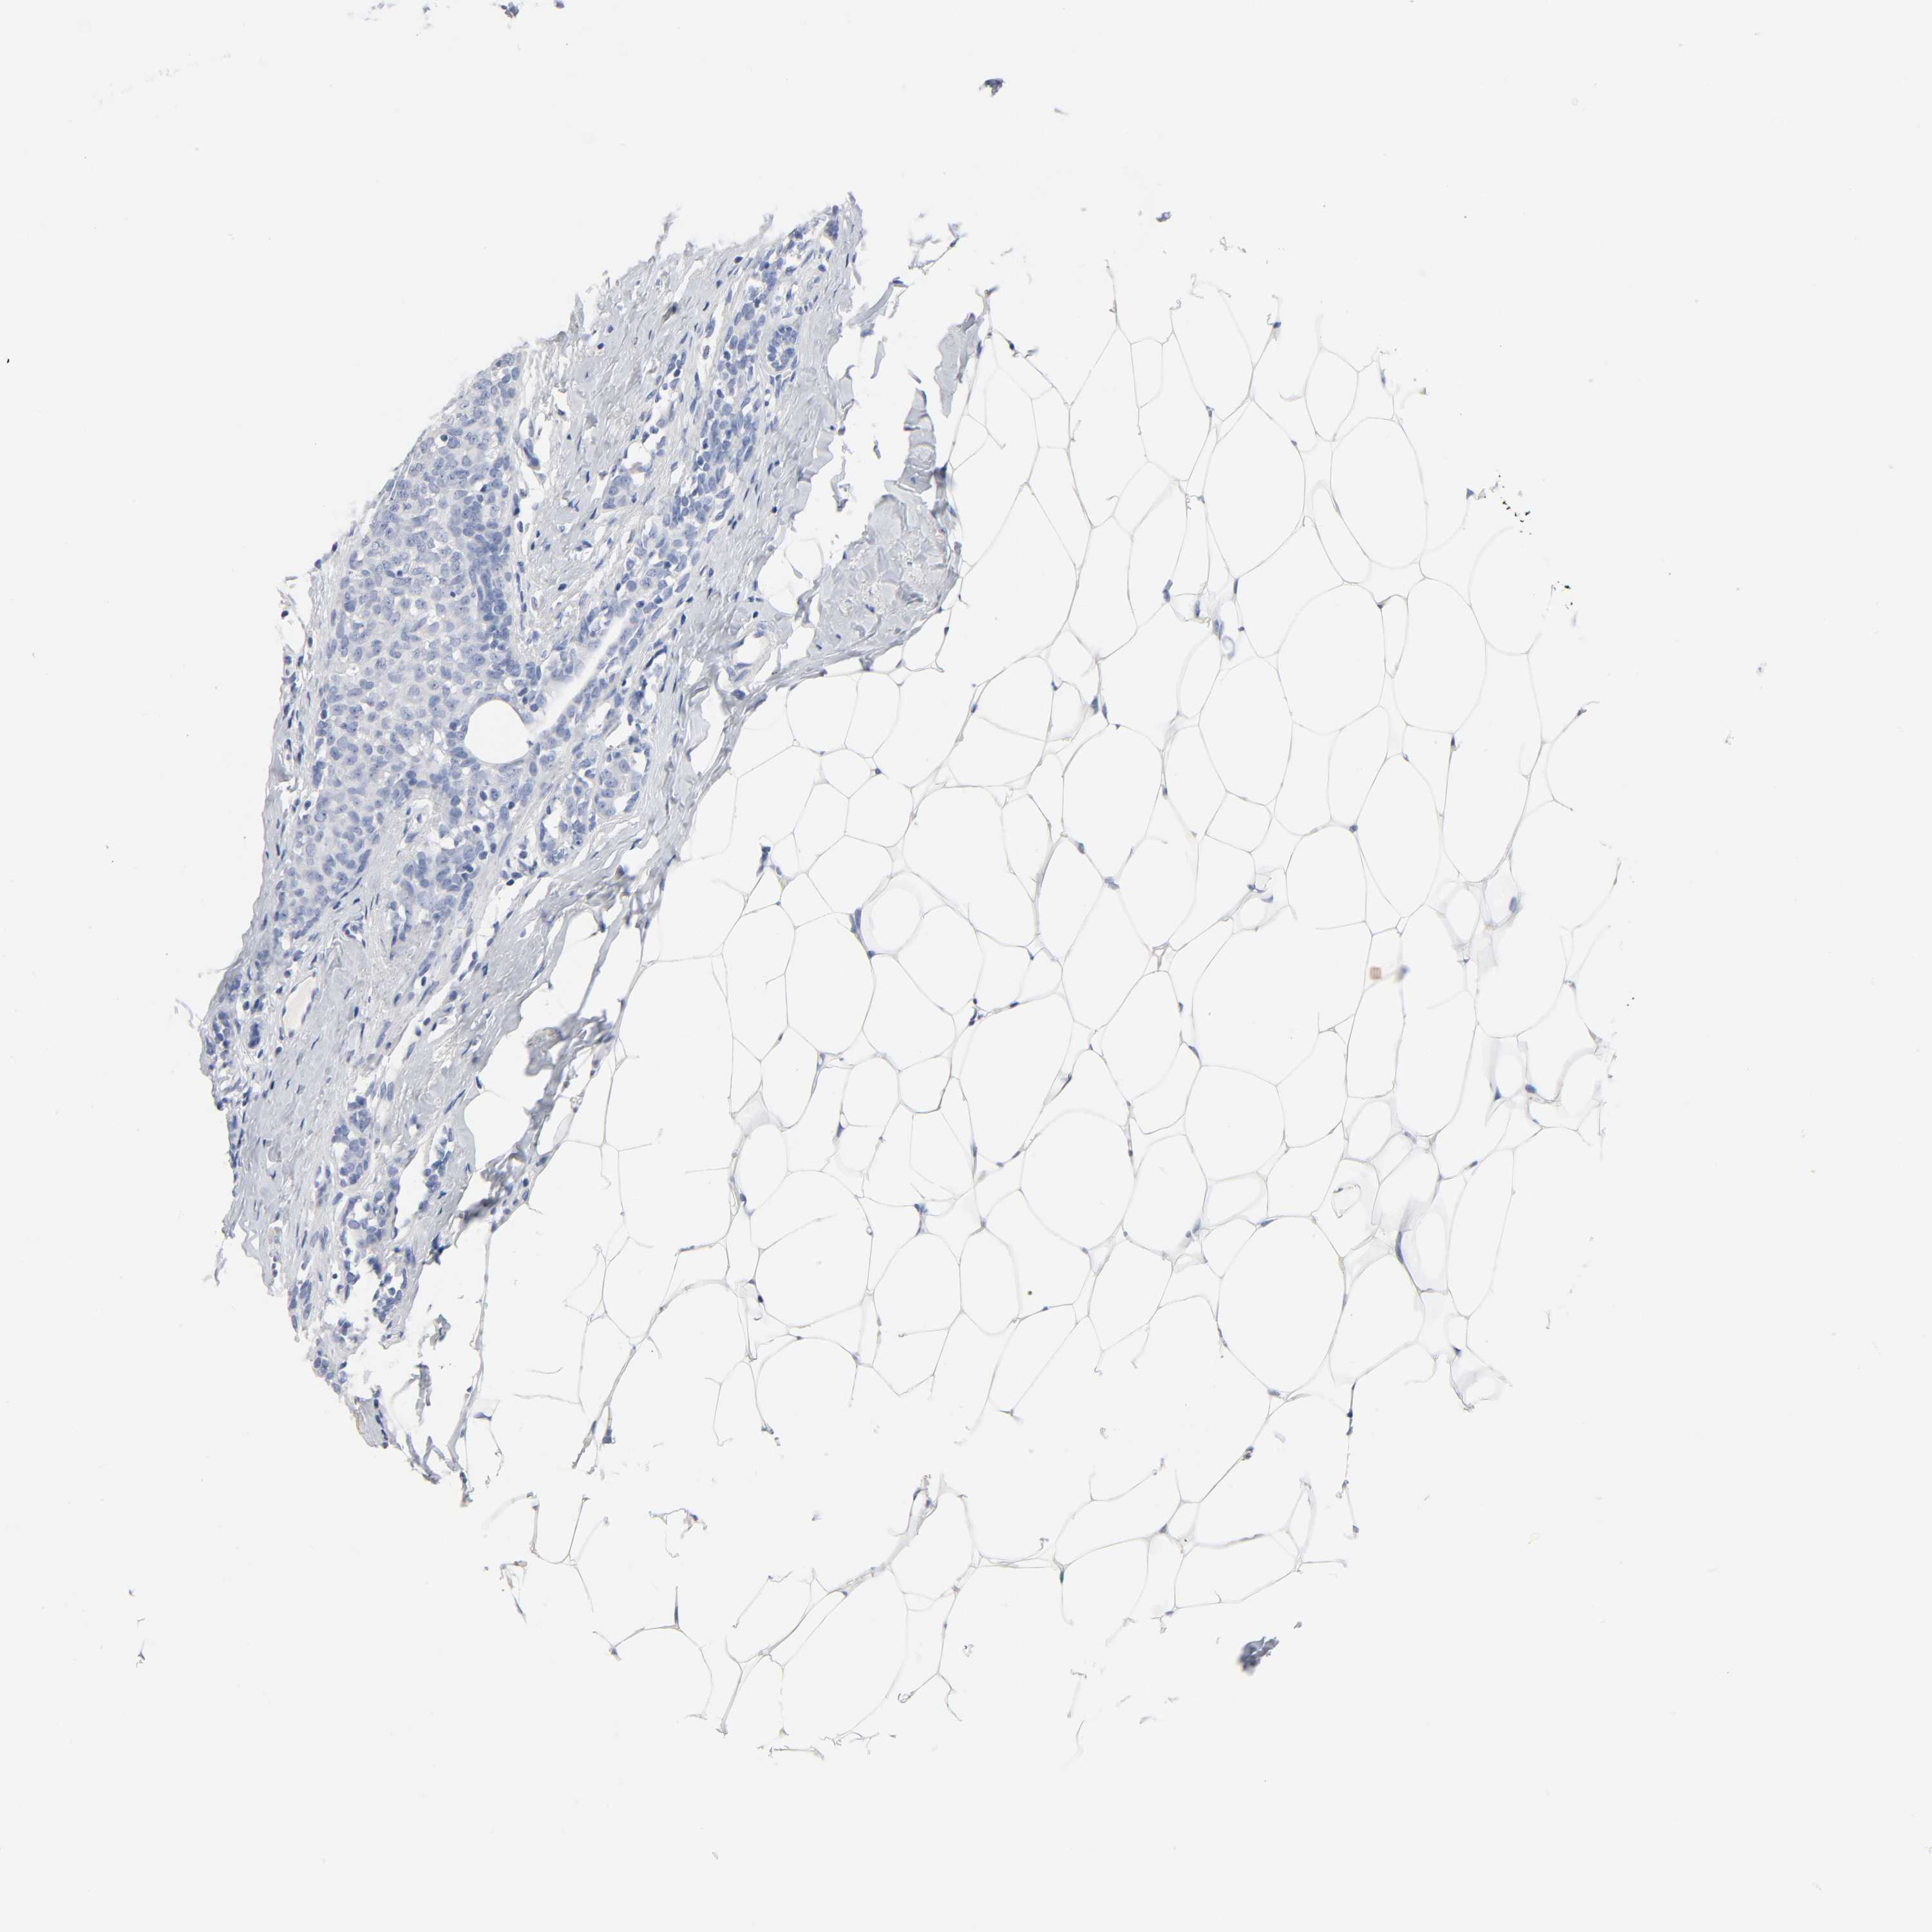

BRCA TCGA BRCA VALIDATION PROTEIN EXPRESSION

ANTIBODIES

AND

VALIDATION